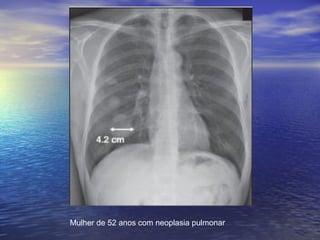

Mulher de 52 anos com neoplasia pulmonar